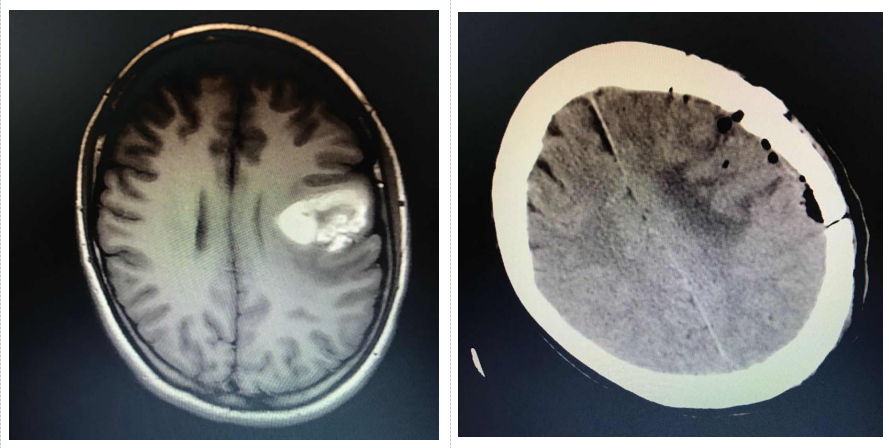

术前:脑血管畸形伴出血;术后:血管畸形已切除 图/医院提供

20岁女大学生,因突然失语伴头痛,辗转当地多家医院,CT检查显示脑出血。后转诊至南方医科大学中西医结合医院神经外科,根据黎同学的病史、CT影像资料,医院为其进一步完善头颅MR检查,确诊脑血管畸形导致的出血。

与家属进行沟通后,陈陆馗主任确认了手术方案。在脑内血肿吸收后,进行左侧中央区颅内血管畸形切除术。在医护人员精心的呵护下,黎同学恢复得很快,语言功能逐渐恢复正常。